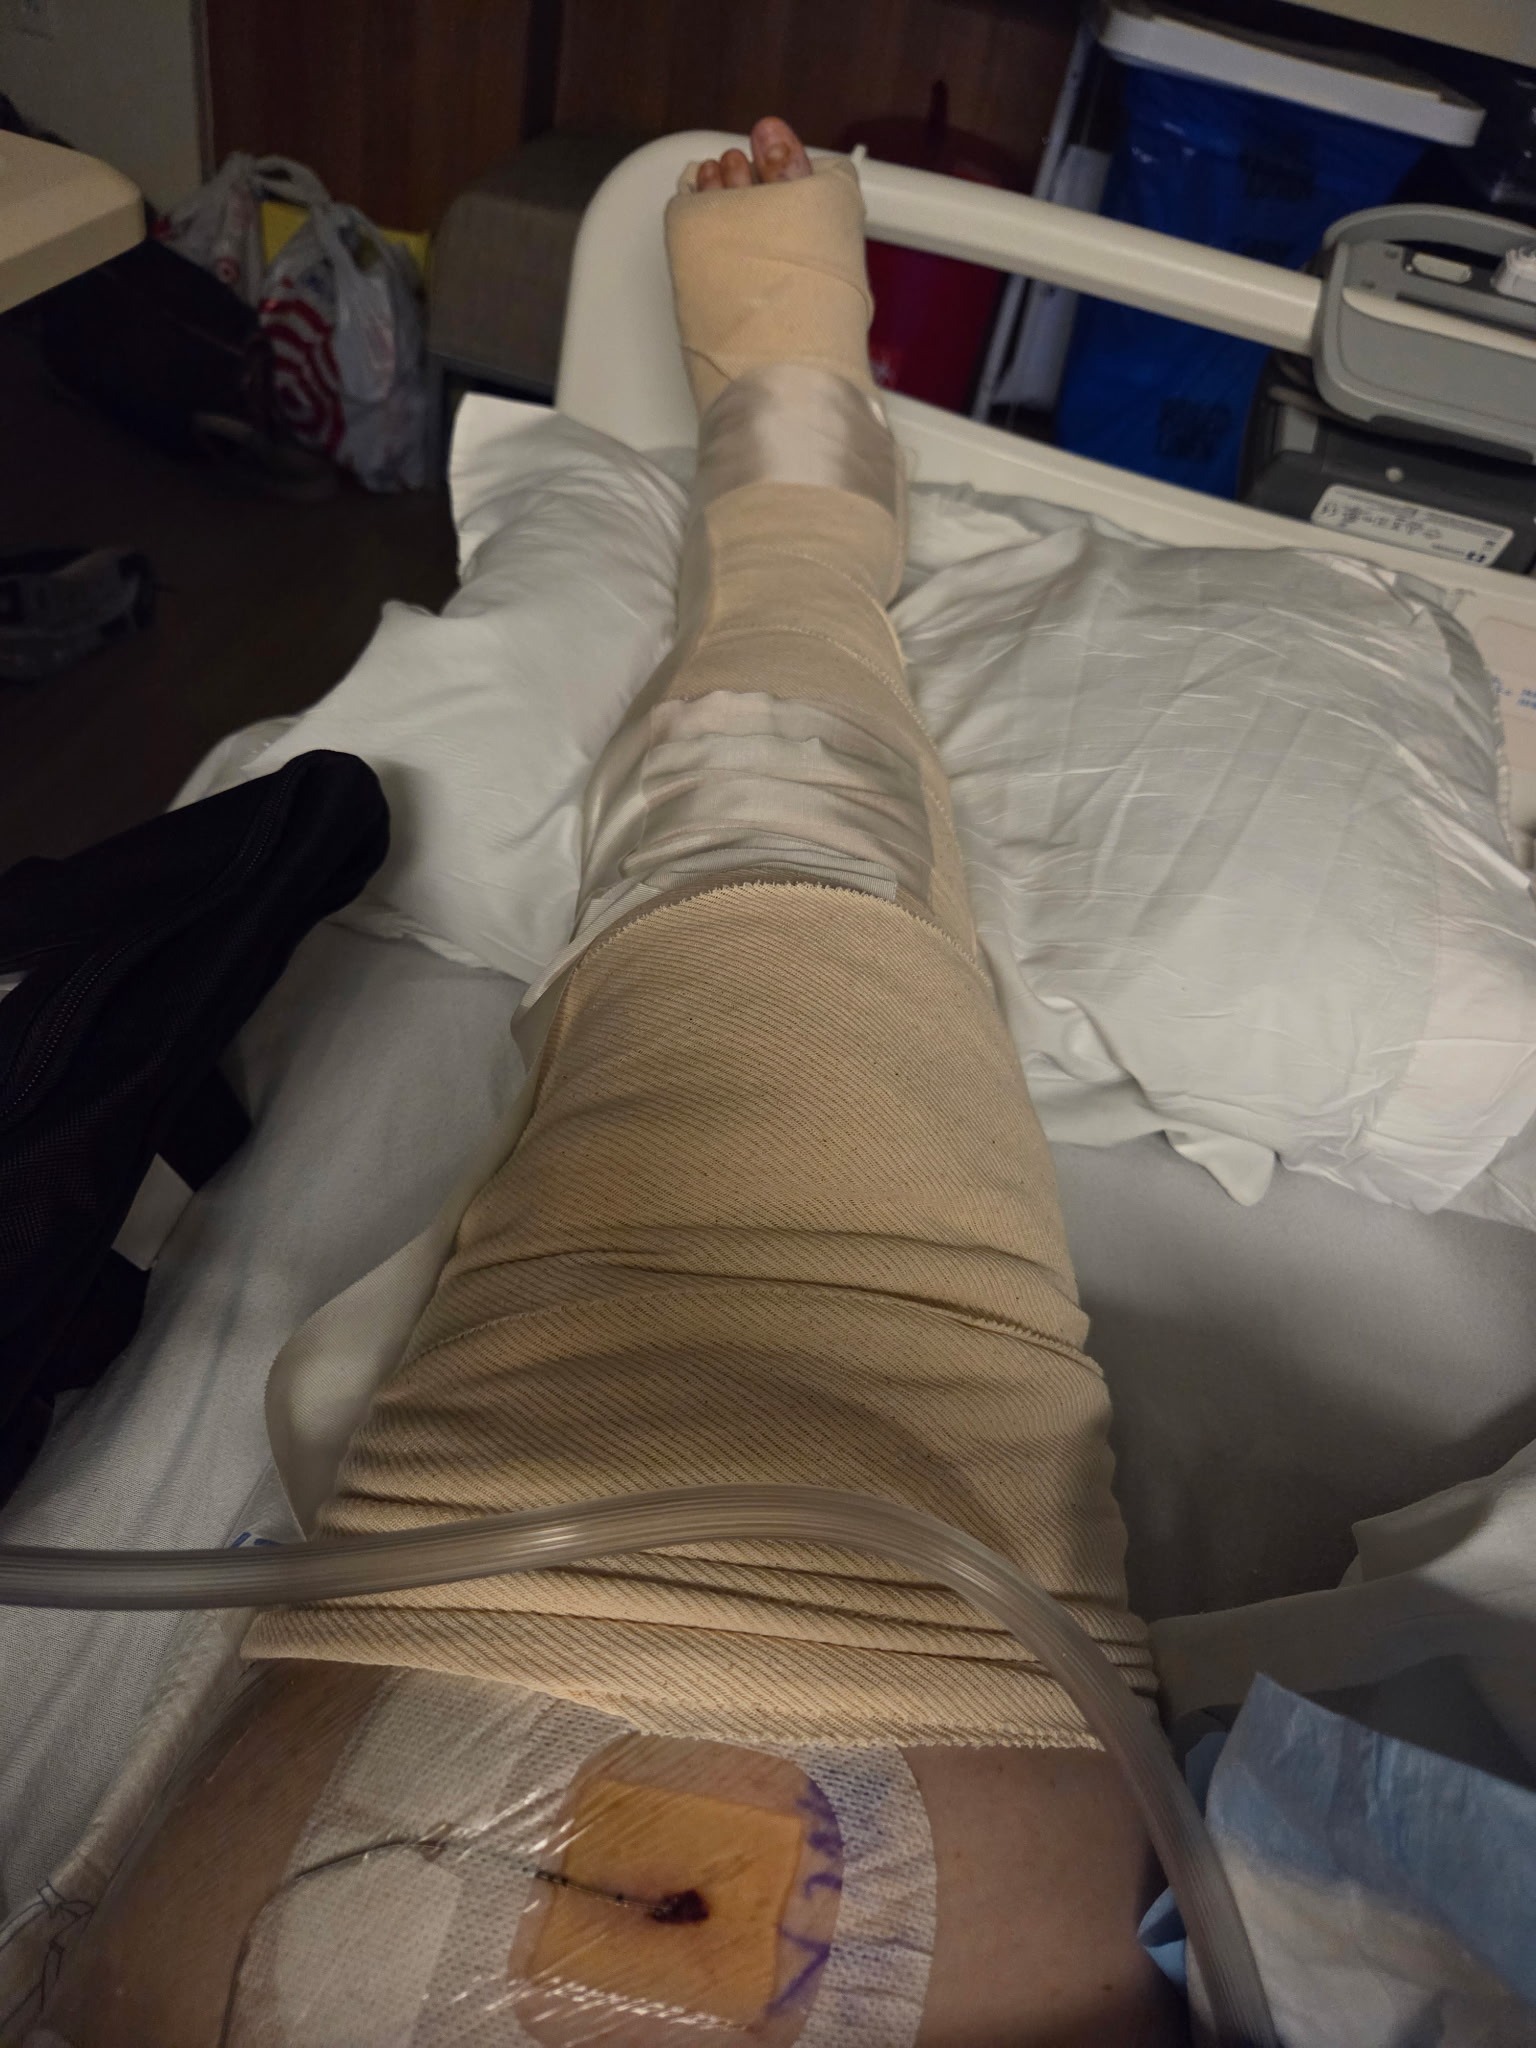

On December 3rd, our dear friend Chelsea was leaving her shift as a postpartum doula when she fell down the base of a narrow staircase at an overnight shift. The fall resulted in 4 breaks in her left leg, 3 of which were spiral fractures of her tibia and fibula. These required emergency trauma surgery and per her surgical team, she is now unable to bear any weight on her left side for at least 2 months. She will not be able to work during this time and she will need daily assistance for basic self-care at home– for example, using a commode, transferring to/from the hospital bed and wheelchair, meal prep, and more.